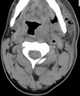

Neck infection